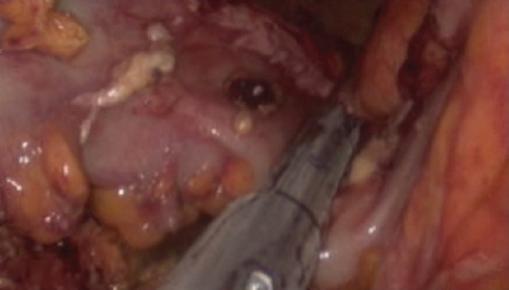

Se decidió realizar exploración quirúrgica de urgencia por abordaje laparoscópico, encontrando material intestinal y purulento libre en la cavidad (Fig. 2), con el ciego perforado hacia la vejiga, observándose el globo de la sonda transuretral (Fig. 3). Se realizó hemicolectomía derecha (Fig. 4) con ileostomía terminal, cierre primario de la perforación vesical en tres planos (Figs. 5 y 6) y colocación de drenaje. La paciente se mantuvo en vigilancia posoperatoria en terapia intensiva, resolvió el cuadro de sepsis abdominal y fue egresada al sexto día a piso para continuar su recuperación a cargo de los servicios de nefrología y cirugía general. En el día 15 de posoperatorio se evidenció una nueva colección intraabdominal en la corredera parietocólica derecha, la cual se trató mediante drenaje percutáneo y antibiótico por vía intravenosa, resolviéndose sin complicaciones. Continuó con evolución tórpida por sus patologías de base, requiriendo múltiples sesiones de hemodiálisis, y finalmente falleció por complicaciones asociadas a la enfermedad renal.